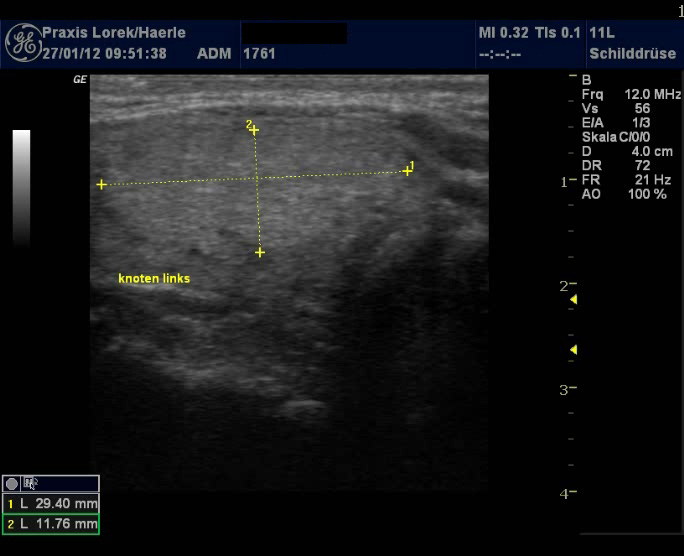

| Abb. 3 und 4:

Ungleichmäßige Echoarmut der Schilddrüse bei einer

27-jährigen Patientin, Schilddrüse mit etwa 19,4 ml leicht

vergrößert, eher hypertrophe Verlaufsform (klassische

Hashimoto-Thyreoiditis), Patientin klagte unter Müdigkeit während

ihrer ersten Schwangerschaft 2005. Pseudoknoten Tirads 3 im linken dorsalen

Lappen. |